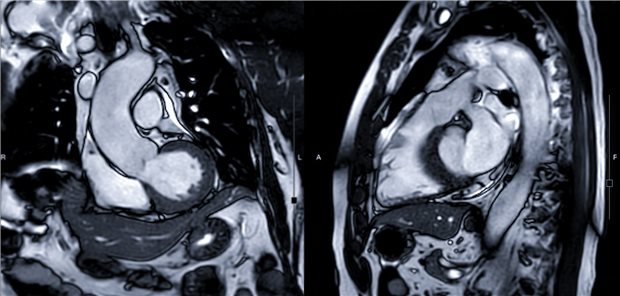

Die Refinanzierung ambulanter Kardio-MRT bleibt mühsam. Umso wichtiger ist eine kluge Indikationsstellung. Bei den Herztagen gab es Tipps für die kardiologische „Triagierung“ in Richtung Kernspin.